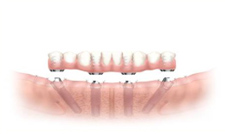

All-on-4 では、臼歯部にインプラントを30-45°傾斜させて埋入することにより、下顎で4本、上顎で4-6本のインプラントで補綴を支持することができます。

インプラント埋入(上顎)

【術後】